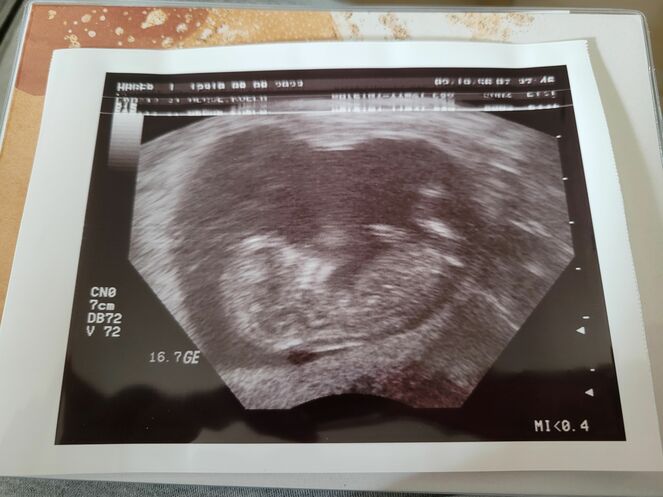

Der erste große Ultraschall - Tagebücher aus der Schwangerschaft von Tatjana aus Nordeifel